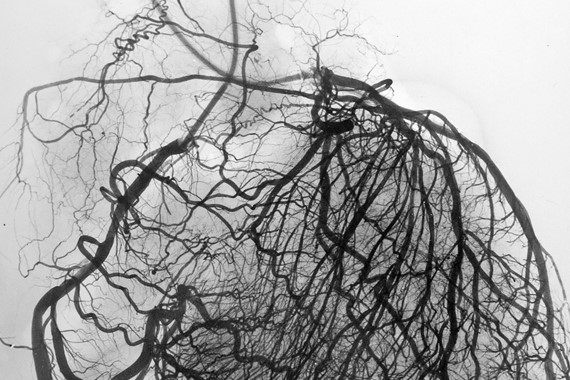

از بررسی لیست بالا مشخص می شود که اغلب عوامل ایجاد کننده تنگی عروق کرونر و رسوب چربی خون در بدن ، بیماریهای منحصر به قلب نیستند بلکه تمام بدن را شامل می شوند. به عنوان مثال کسی که بیماری دیابت دارد یا فشار خون بالای درمان نشده دارد ، این بیماری در سراسر بدن وی فعال است و عملکرد آن محدود به قلب و عروق کرونر قلب نیست. لذا وقتی که یک فرد بیماری رسوب چربی خون یا آتروسکلروز دارد این بیماری یک بیماری سیستمیک و مربوط به کل بدن است. لذا اگر یک فرد دارای تنگی مهم داخل عروق کرونر است این بیماری مربوط به یک قسمت از عروق کرونر وی نمی شود و در اغلب بیماران تنگی های گسترده و پراکنده ای را در تمام بستر عروقی قلب و حتی عروق غیر قلبی ، می توان مشاهده کرد.

اول اینکه در زمان تعبیه استنت قلبی یا عمل بای پس عروق تنگ قلب ، صرفا نواحی با شدت تنگی زیاد ( بیش از 70 درصد مقطع رگ ) درمان می شوند و برای سایر نواحی قلب که دارای تنگی های کمتر از آن هستند ، کاری صورت نمی گیرد. اگرچه تنگی های مهم عروق قلبی منشا اصلی علایم بیماران و عامل مهم ایجاد حمله های حاد قلبی هستند ولی تعداد قابل توجهی از حملات قلبی می توانند در تنگی های متوسط و حتی خفیف عروق کرونر اتفاق بیفتند و چون تعداد این نوع از تنگی های عروق قلبی و پلاک های چربی خون قابل توجه است لذا بعد از عمل جراحی قلب هم احتمال ایجاد تنگی مجدد و بروز حملات قلبی وجود دارد.